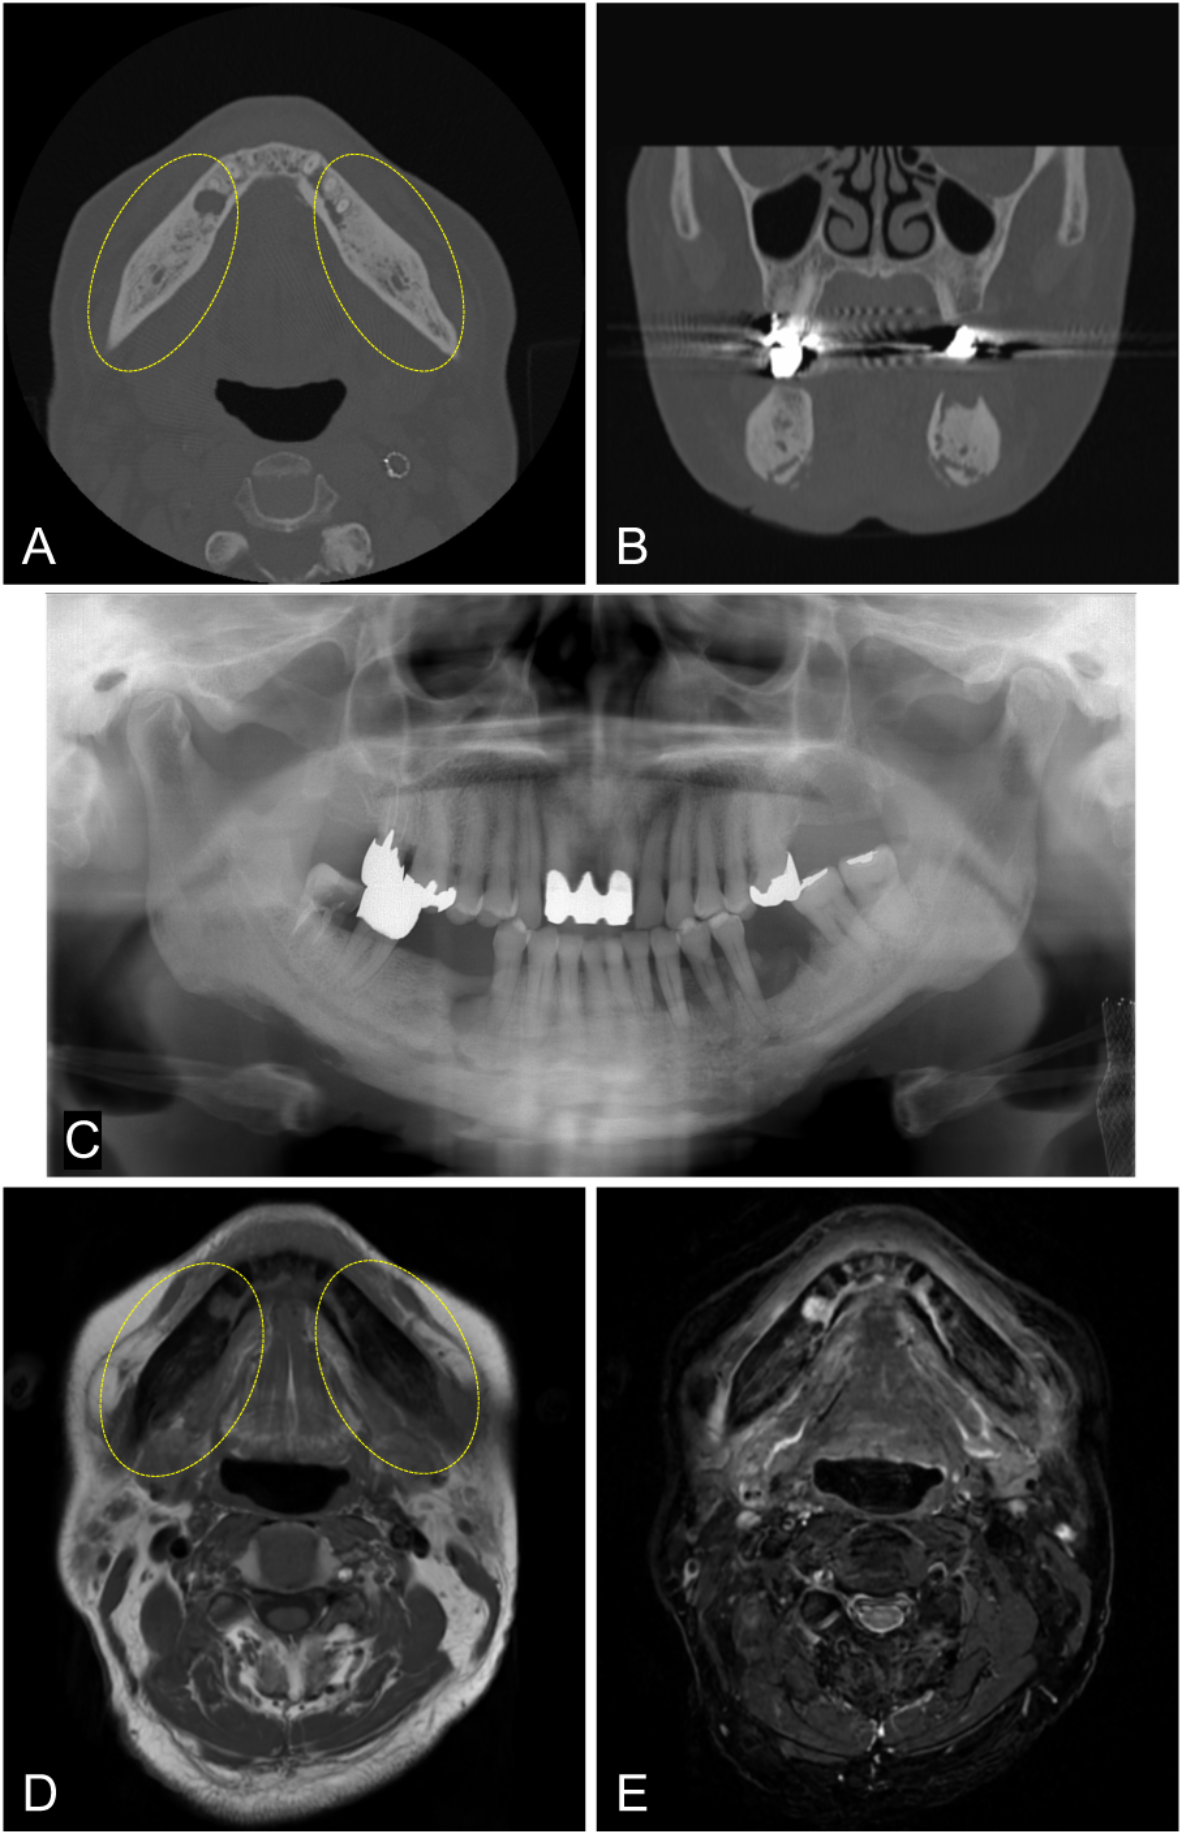

Fig. 2

Case with osteosclerosis. A 72-year-old male with a history of denosumab use for bone metastasis from bile duct cancer. Although he underwent extraction of the right mandibular second premolar at a dental clinic after a 2-month hiatus from medication, he was referred to our hospital due to treatment for bone exposure. (A, B) CT images (bone mode) showing an increase in CT values in the mandibular trabecular bone on both sides as well as the extraction socket of the right mandibular second premolar (ellipses). (C) Panoramic X-ray image revealing increased radiopacity in the mandibular trabecular bone on both sides. (D, E) T1-weighted MR image and T2-weighted fat-suppressed MR image demonstrate a sclerotic area in the same region, and the bone marrow signal in that area shows low signal intensity (ellipses).